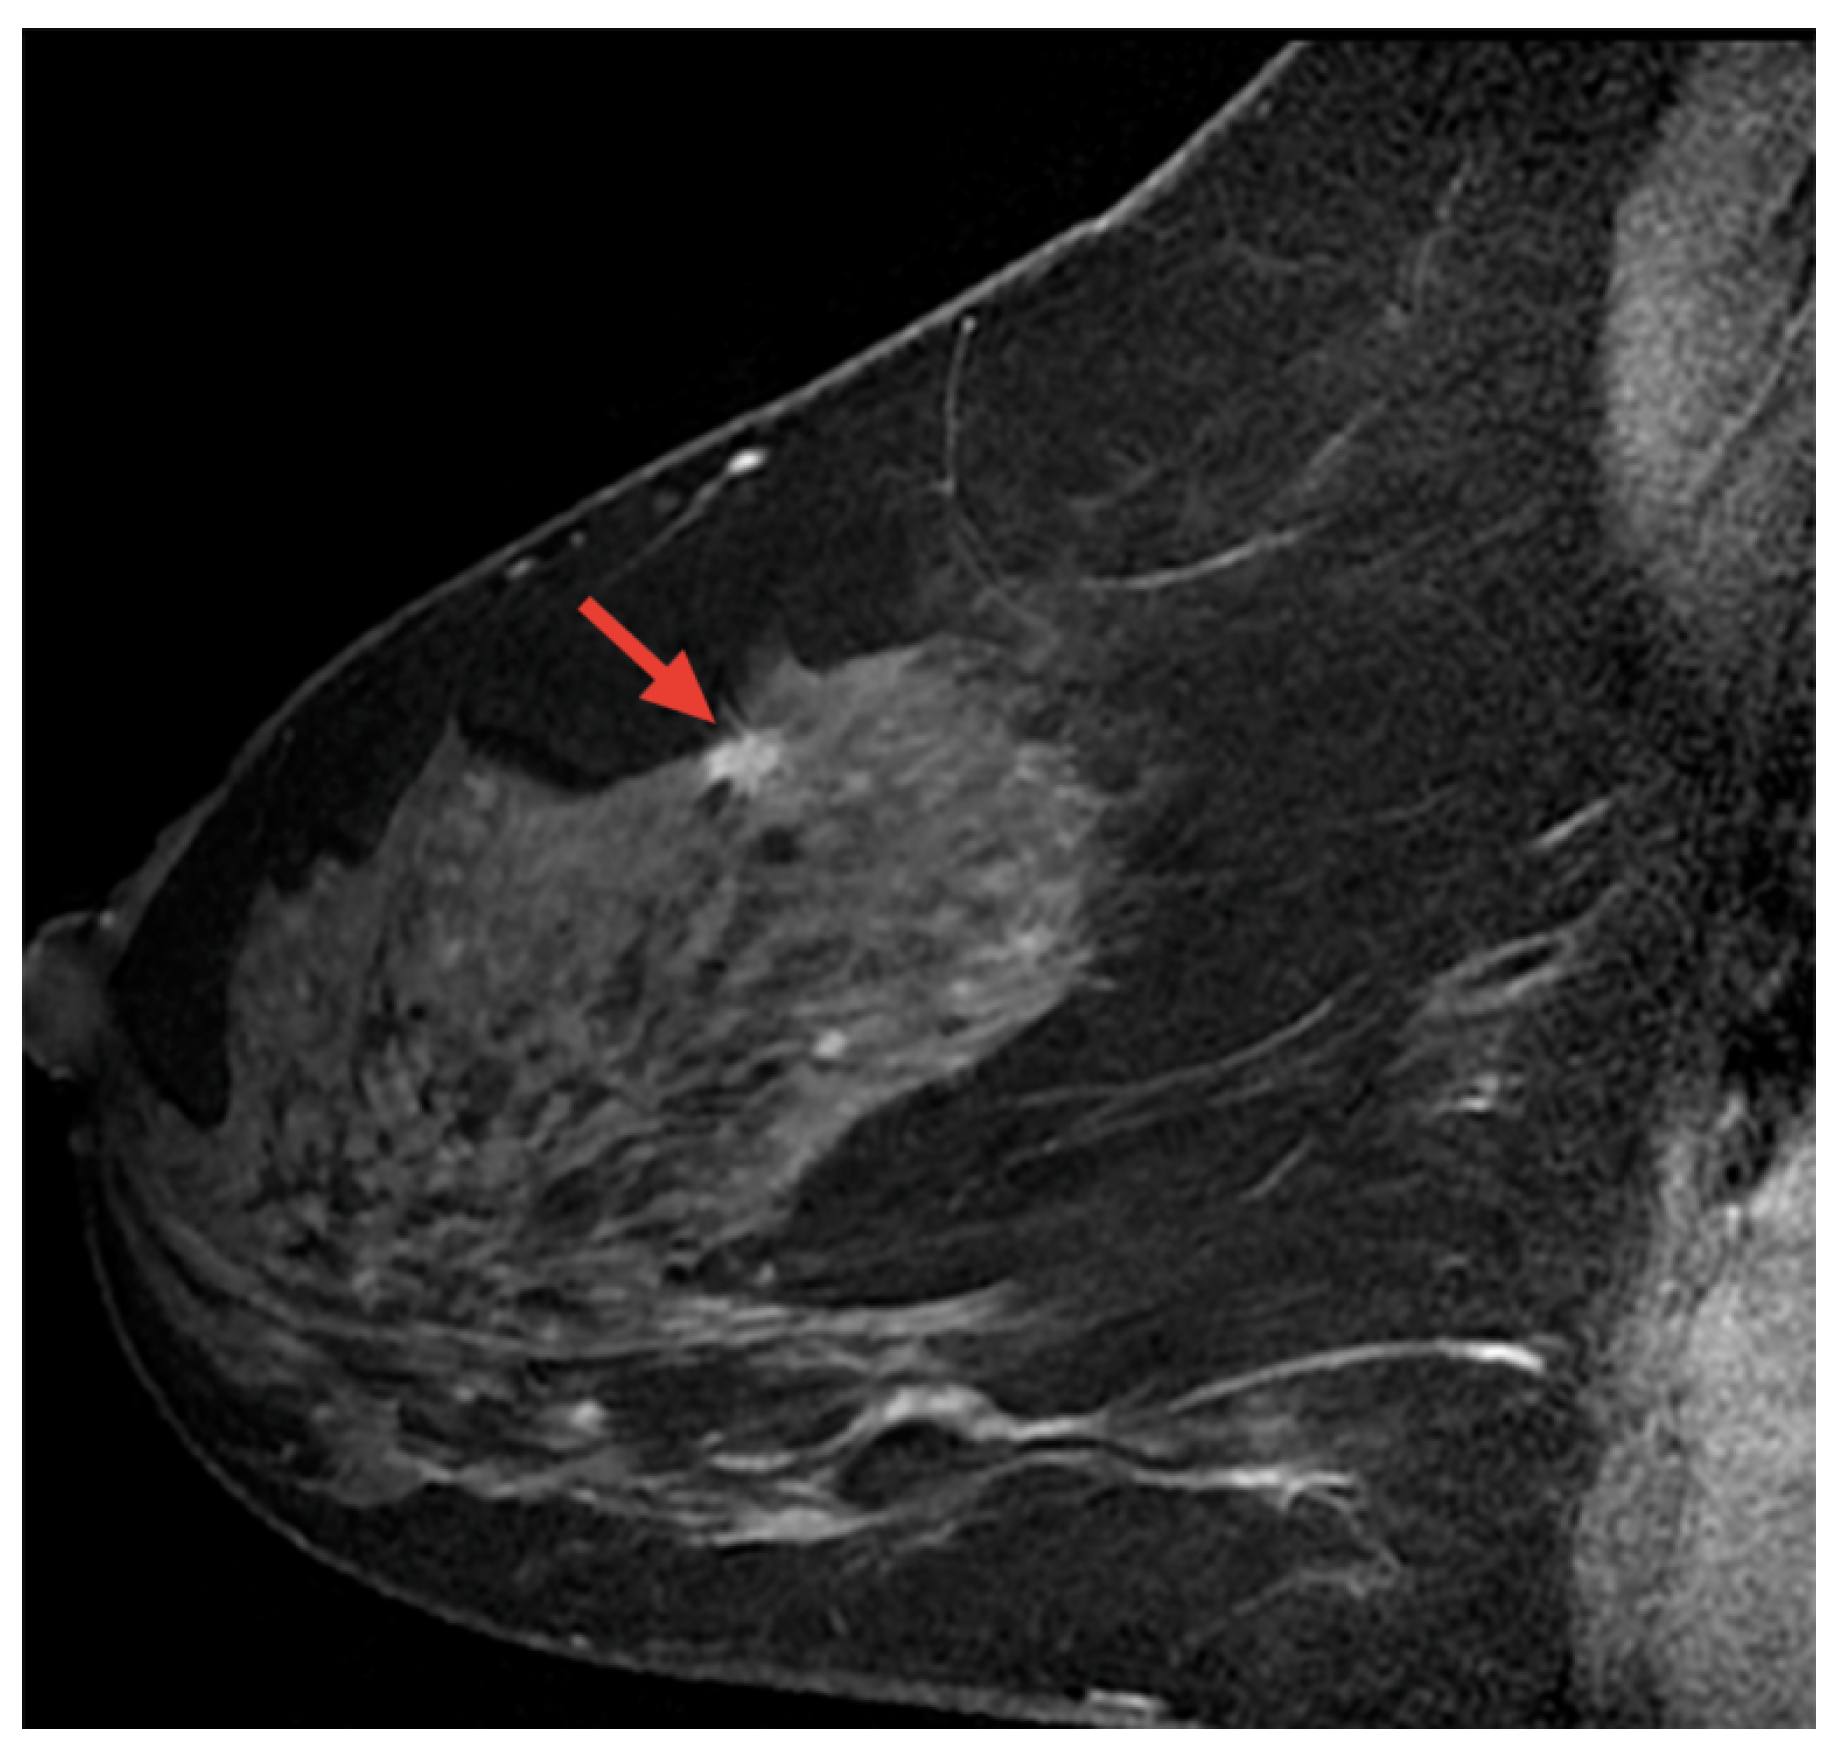

8.3. Breast Cancer Detection Based on Magnetic Resonance Imaging (MRI) Images

Magnetic resonance imaging (MRI) is a safe, non-invasive technique that uses magnetic fields and radio waves to produce detailed internal body images. MRI is employed in the diagnosis and monitoring of conditions such as soft tissue abnormalities, tumors, and brain and spinal disorders. This section highlights AI-based methods for BC detection using MRI images [115]. Figure 17 displays a sample MRI image with a highlighted area, marked by the red arrow, indicating a potential abnormality for further examination.

Figure 17.

A sample MRI image [92,116].